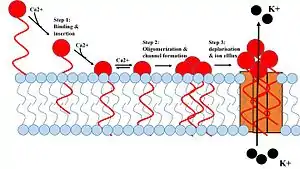

1. Daptomycin binds and inserts into the cell membrane. 2. It aggregates in the membrane. 3. It alters the shape of the membrane to form a hole, allowing ions in and out of the cell easily. | |

Daptomycin has a distinct mechanism of action, disrupting multiple aspects of bacterial cell membrane function. It inserts into the cell membrane in a phosphatidylglycerol-dependent fashion, where it then aggregates. The aggregation of daptomycin alters the curvature of the membrane, which creates holes that leak ions. This causes rapid depolarization, resulting in a loss of membrane potential leading to inhibition of protein, DNA, and RNA synthesis, which results in bacterial cell death.[25]

It has been proposed that the formation of spherical micelles[26] by daptomycin may affect the mode of action.